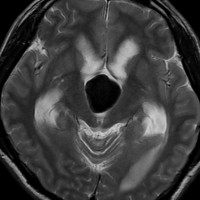

典型的な神経腸嚢胞 neurenteric cyst

左のT2強調画像で等信号,中のT2*で高信号,右はCISS画像です。

T1強調画像では,のう胞周囲の高信号の部分は半固体で,中心部の高信号はドロドロの粘液でした。基本的にガドリニウム増強はされません。まれに薄い膜状に一部が増強されることがあります。

境界明瞭は袋状の腫瘍です。椎骨動脈や脳底動脈を包み込むようにふくらんでいます。

左外側後頭下開頭という小さな開頭手術だけで全摘出しました。術後は幸い何の症状も出ていません。この例は脳幹部に食い込まないもので,運良く全摘できたのですが,そうはいかないものもあります。